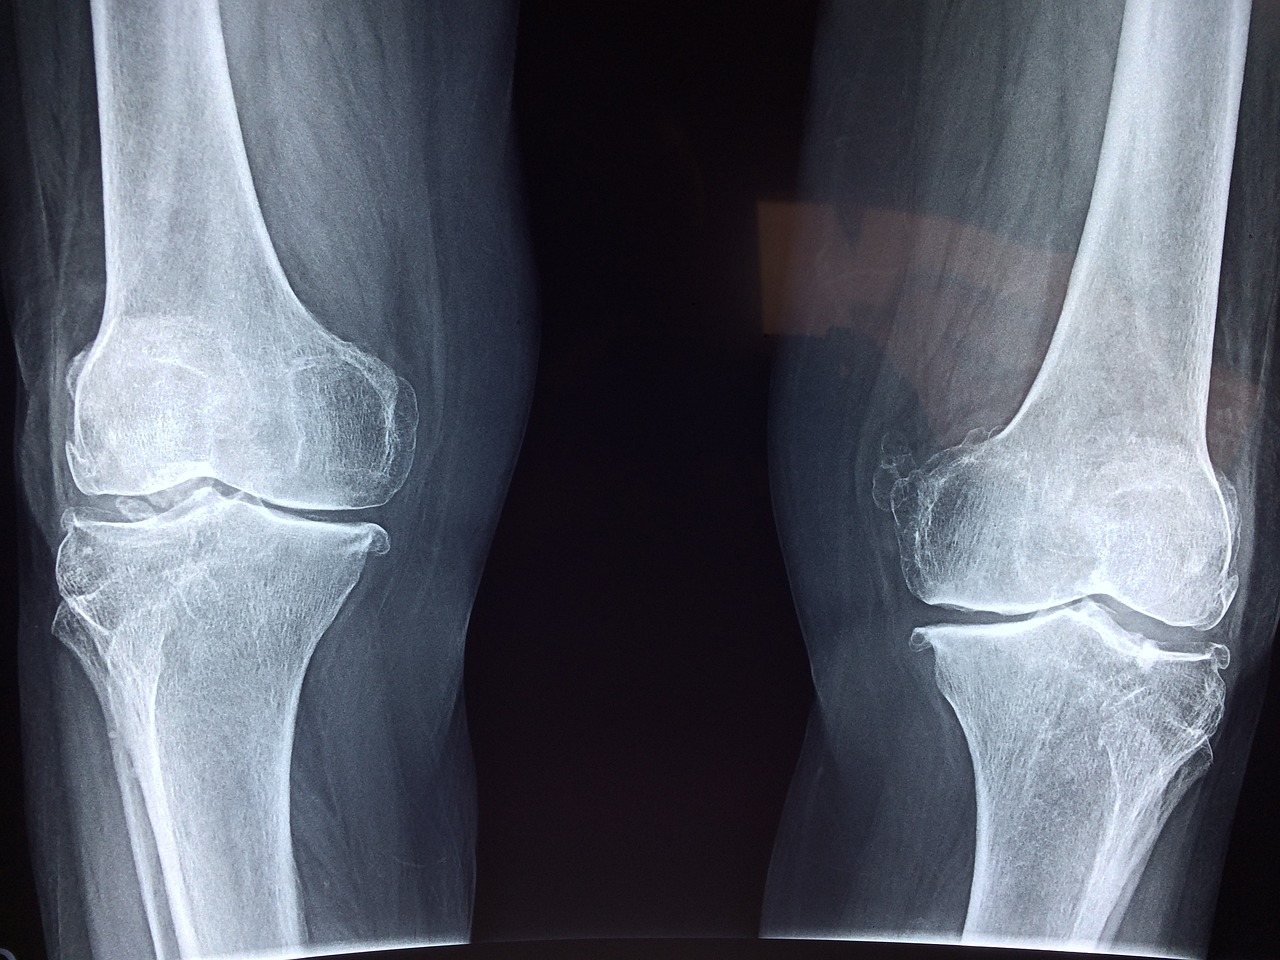

암환자 요양등급 신청방법은 일반적인 노인장기요양 등급과는 다소 차이가 있습니다. 암 자체만으로는 장기요양등급을 받기는 어렵지만, 암 치료로 인해 일상생활이 어려운 경우, 특히 체력 저하나 후유증으로 일상생활동작(ADL) 수행이 어려운 상태라면 신청 가능합니다.

제가 도와드렸던 한 사례는 항암 치료 중이신 환자분이 암 관련 피로와 부작용으로 거의 누워 지내는 상황이었고, 이 경우 등급 4~5급 판정을 받은 사례입니다. 핵심은 노인성 질환 여부가 아닌, 기능저하로 인한 요양 필요성을 증명하는 것이죠.

서류에는 반드시 의사 소견서 또는 진단서가 포함되어야 하며, 환자의 일상생활 수행 어려움을 명확히 기재해야 합니다. 방문조사에서도 의료정보가 중요한 참고자료가 되니, 암환자의 경우 전문의의 상세한 진단서가 큰 도움이 됩니다.